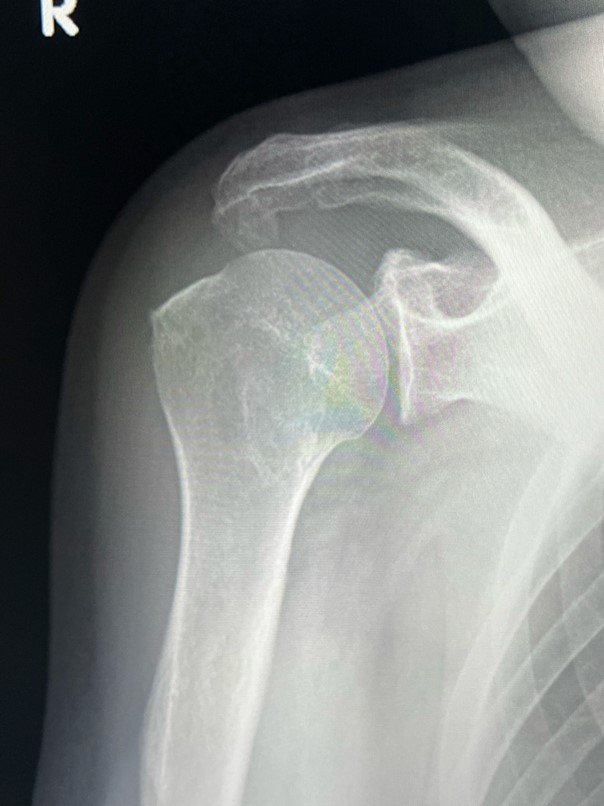

五十肩のレントゲン検査

まず整形外科で行われる基本検査「レントゲン(単純X線検査)」。この検査では五十肩特有の所見はほとんどありません。むしろ、「レントゲンに異常がないから五十肩だね」という説明を受けることもあるかと思います。 なぜなら、五十肩で炎症が起こる部位は関節包にしろ腱にしろ滑液包にしろ、レントゲンに写らない部位だからですね。 しかし、撮像する意味がないわけではありません。五十肩以外の疾患がないかをチェックすることができます。その代表として2つ。 石灰沈着性腱板炎で認められる腱板の中の石灰はレントゲンに写りますし、また、軟骨がすり減ってしまう変形性肩関節症もレントゲンで判定できます。